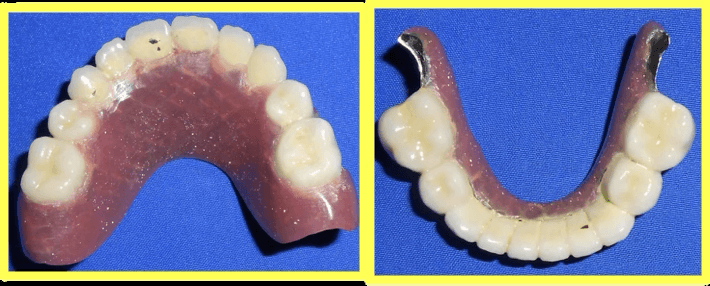

Endodontic treatment performed on all remaining deciduous teeth to ensure they could serve as stable abutments for telescopic prosthesis.

Custom telescopic copings were designed and fabricated to fit over prepared teeth, providing retention and support for the removable prosthesis.

Upper and lower telescopic removable metallic PFM prosthesis was carefully fitted, adjusted, and delivered to restore complete dental function and aesthetics.